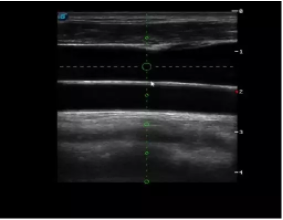

多數(shù)的生殖科醫(yī)生對于受精卵的植入采用憑經(jīng)驗操作或是使用傳統(tǒng)腔內探頭引導,同樣存在手術空間小、受精卵放置位置不確定等風險。專業(yè)的宮腔專用探頭,配合專用的窺器使用,為醫(yī)生提供最大的手術視野。

胎移植臨床圖